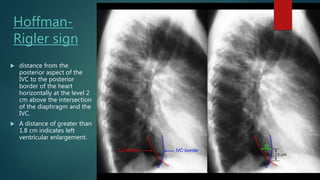

Hoffman-

Rigler sign

 distance from the

posterior aspect of the

IVC to the posterior

border of the heart

horizontally at the level 2

cm above the intersection

of the diaphragm and the

IVC.

 A distance of greater than

1.8 cm indicates left

ventricular enlargement.